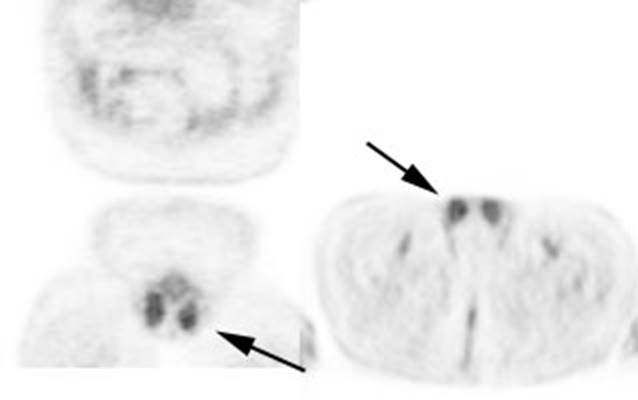

Figure 25 - Normal

testicular activity: Mild

symmetric testicular uptake can be seen (black arrows)